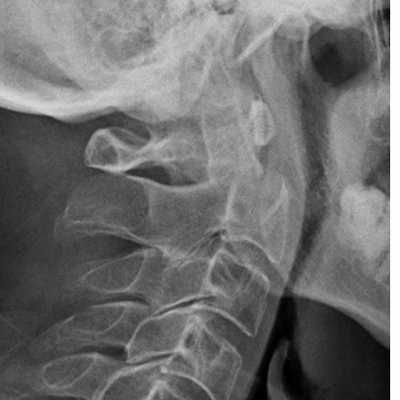

Латеральная проекция

Латеральная проекция шейного отдела позвоночника представляет собой наиболее важное рентгенологическое исследование повреждения шейного отдела позвоночника. Перед выполнением любых других снимков необходимо получить и изучить боковую рентгенограмму. Необходимо визуализировать все 7 шейных позвонков и соединение C7-T1, поскольку шейно-грудной отдел является частым местом травматических повреждений. Адекватная визуализация C7-T1 может быть ограничена мягкими тканями в области плеча и может быть улучшена либо за счет вытяжения за руки (при отсутствии травмы руки), либо за счет позы пловца (одна рука вытянута над головой). Иногда повторная боковая рентгенограмма с удаленным шейным воротником может прояснить подозрительные поражения.

Первое наблюдение, которое необходимо сделать на боковой рентгенограмме - это выравнивание тел позвонков. Необходимо выровнять передний и задний края тел позвонков, спиноламинарную линию и кончики остистых отростков. Любой «шаг» в выравнивании считается ненормальным и должен рассматриваться как свидетельство повреждения связки или скрытого перелома; таким образом, иммобилизация шейного отдела позвоночника должна сохраняться до постановки окончательного диагноза.

Если выравнивание нормальное, остистые отростки исследуются на предмет расширения межостистого пространства. Расширение предполагает травму или перелом связки.

Затем следует оценить изгиб позвоночника. Угол наклона более 11° на любом уровне шейного отдела позвоночника считается ненормальным и в контексте травмы шейного отдела позвоночника следует рассматривать как вторичный по отношению к травме или перелому связки, пока не будет доказано обратное. Ширина позвоночного канала на боковой рентгенограмме должна быть более 13 мм. Измерение менее 13 мм может быть признаком надвигающегося поражения спинного мозга.